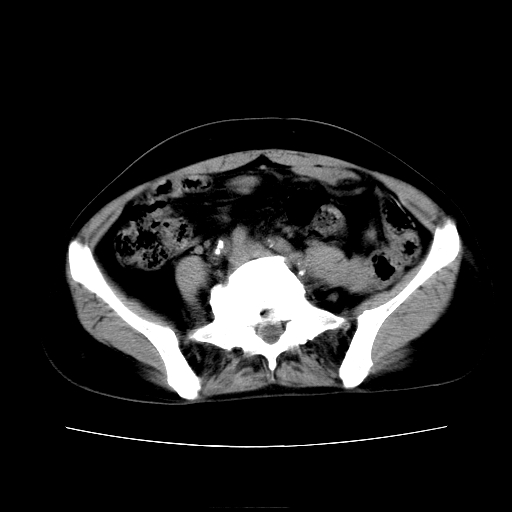

女45y多次(7次)碎石,结果不理想!曾碎石后尿出小碎石,仍腰痛,要求ct,其它不详.本人更倾向于钙化斑!无肾实质破坏,积水等提示集合系统无梗阻.另外腹腔多处钙化.是否结核后改变!谢谢赐教!

1)双肾结石。2)脾脏钙化灶。3)腹膜后多发淋巴结钙化。

尿路结石与腹部淋巴结钙化共存,建议v尿路造影检查,免得钙化灶冤枉为结石受罚。